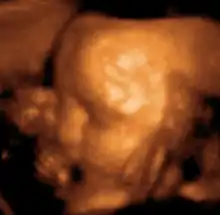

Акушерство, гинекология и пренатальная диагностика

Ультразвуковое исследование используется для изучения внутренних половых органов женщины, состояния беременной матки, анатомии и мониторинга внутриутробного развития плода.

Этот эффект широко применяется в акушерстве, так как звуки, идущие от матки, легко регистрируются. На ранней стадии беременности звук проходит через мочевой пузырь. Когда матка наполняется жидкостью, она сама начинает проводить звук. Положение плаценты определяется по звукам протекающей через неё крови, а через 9 — 10 недель с момента образования плода прослушивается биение его сердца. С помощью ультразвукового исследования можно также определять количество зародышей или констатировать смерть плода.